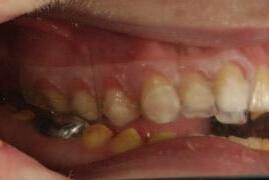

bicortical screws, and without insertion of intermaxillary fixation (IMF) screws. Orthodontic brackets were used to stabilise the occlusion for six weeks ( Figure 6 ).

Two weeks after the surgery, the patient reported that the pain was significantly improved, with only a tingling sensation remaining. The feeling of pressure was completely relieved. At one-year follow-up, sensation was restored and no pain was reported.